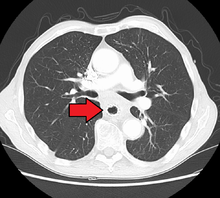

If the cancer has spread elsewhere, symptoms related to metastatic disease may appear. Common sites of spread include nearby lymph nodes, the liver, lungs and bone.[12] Liver metastasis can cause jaundice and abdominal swelling (ascites). Lung metastasis can cause, among other symptoms, impaired breathing due to excess fluid around the lungs (pleural effusion), and dyspnea (the feelings often associated with impaired breathing).

Additional testing is needed to assess how much the cancer has spread (see #Staging, below). Computed tomography (CT) of the chest, abdomen and pelvis can evaluate whether the cancer has spread to adjacent tissues or distant organs (especially liver and lymph nodes). The sensitivity of a CT scan is limited by its ability to detect masses (e.g. enlarged lymph nodes or involved organs) generally larger than 1 cm. Positron emission tomography is also used to estimate the extent of the disease and is regarded as more precise than CT alone. Esophageal endoscopic ultrasound can provide staging information regarding the level of tumor invasion, and possible spread to regional lymph nodes.